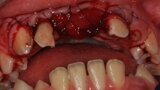

Ryc. 3_Zęby 11 i 21 po ekstrakcji.